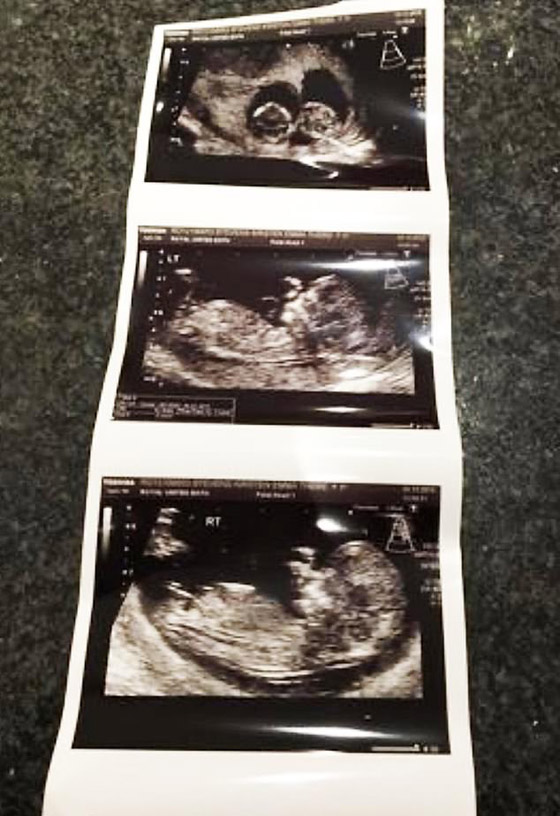

حسب تقرير لصحيفة بريطانية، الثلاثاء، فإن التوأمين، أصبح لديهما أعياد ميلاد مختلفة، أما السبب فيعد لكونهما رأيا النور في منتصف الليل. في تعليقها على الأمر تقول الأم كريستن: "طوال حملي، قيل لي إنهما غير متطابقين، وقد آمنت بذلك"، لكن بعد ولادتهما في 6 و7 يونيو/حزيران، بَدَآ يبدوان متشابهين للغاية. وقد كانت هناك فرصة بنسبة 30% فقط أن يكونا متطابقين بسبب وجودهما في كيسين منفصلين.

لكن الأم تقول إن الجميع واجه صعوبات كبيرة ليتمكن من التمييز بينهما وقررت إجراء اختبار جيني للاختبار، وهو ما أكد التماثل. كما قيل لكيرستن إن هوغو وليو توأمان ثنائيا المشيمة، مما يعني أن كل توأم له أكياس مشيمية وسلوية خاصة به، وهو الأكثر شيوعاً في التوائم غير المتماثلة. وهذا بالضبط ما أظهرته النتائج، وتضيف أيضاً: "بعد أن اطلعنا على الأخبار، كنا سعداء للغاية".